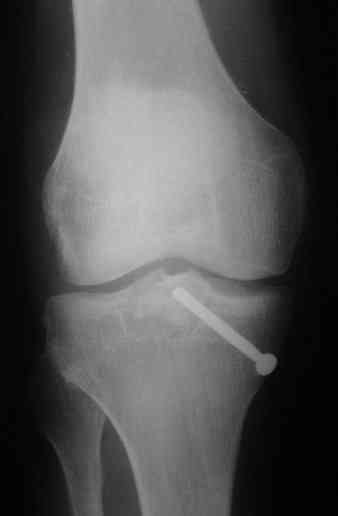

Операция завтра.По рекомендации наших зарубежных коллег выбрали заднемедиальный доступ с фиксацией пластиной и 2.7мм винтами.От Александра Николаевича уже получен наказ, о постоянном участии в операции фотоаппарата,постараюсь реализовать и ваш наказ тоже;-).Спасибо за высказанное мнение.

Для фиксации переломов тибиал плато обычно применеяется техника создания buttress, пластинами с угловой стабильностью, но в данном случае эпифизарный фрагмент очень тонкий на всем протяжении и фиксировать такой перелом невозможно обычными традиционными методами фиксации.

Для лечения таких эпифизарных переломов применяется техника "создания исскуственного края тибиал плато".

Изгибаясь по контуру медиального эпифиза полу-или 1/3 тубулярные пластины создают медиальный край большеберцовой кости.

Радиально проведенные, через пластину и в эпихондральной зоне (пластина действует как шайба) тонкие 2.7 или 3.5 мм кортикальные шурупы до латерального кортекса создают адекватную фиксацию.

Операция из разряда травматологической "экзотики" прошла успешно. Доступ понравился:анатомичный, хорошая визуализация, удобно работать и оператору и ассистентам. Наложили пневможгут, но воспользовались им только на этапе ревизии сустава. Фрагмент развернулся на 90 град. на 2-ух "жгутах": медиально - сухожилие m.semitendinosus, латерально - задняя крестообразная связка. Мобилизовали,развернули и уложили на место без особого труда. Фиксировали отмоделированной 1/3-трубчатой пластиной. Мениск оказался неповрежден. Сустав стабилен. Обошлись без

иммобилизации, планируем начать ранние движения. Остальное на фото, дополнительно приложены корональные срезы КТ.

It is of course only butress, an artificial border of the plateau.